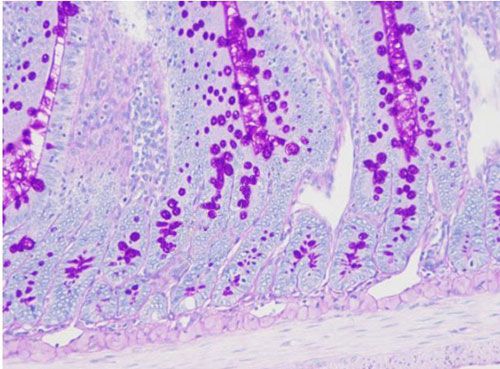

PAS染色又称过碘酸雪夫染色,糖原染色。一般用来显示糖元和其它多糖物质。过碘酸能使细胞内的多糖乙二醇基氧化成二醛,再与Schiff氏液的无色品红结合,红色,定位于胞浆上

PAS染色—小鼠肠

糖原、中性粘液物质、软骨基质、植物的真菌和细胞壁、上皮的基膜等均呈紫红色,细胞核浅蓝色